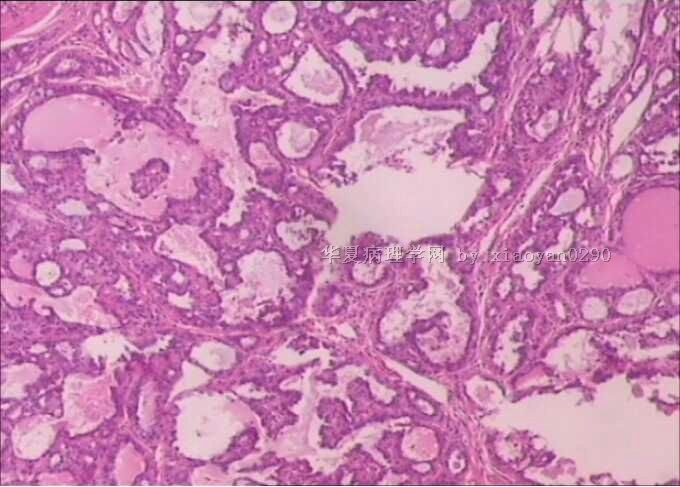

标本名称:  甲状腺肿物

肉眼检查:  组织一块1.7x1.5x1.0cm,无包膜,切面灰白色。

临床诊断:结甲  免疫组化:TG(+)  CK19(+)

• 甲状腺乳头状癌?图1

没有高倍,核特征看不出来,从低倍看,有乳头结构,核偏大也较密集,考虑乳头状癌。